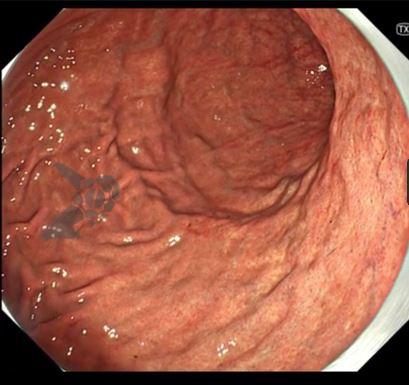

1. TXI (TeXture and color enhancement Imaging)

O TXI é uma tecnologia de imagem realçada. Basicamente, o que o sistema faz é processar a imagem com luz branca após a captura, melhorando sua nitidez. Primeiramente, a imagem capturada é dividida em dois componentes (textura e cor); depois, cada componente é realçado e então a processadora as une de novo e entrega uma imagem com mais qualidade. O resultado é um aumento da claridade nas partes escuras, assim como uma maior nitidez das cores.

Existem dois modos:

TX 1: realça tanto a cor quanto a estrutura.

TX 2: realça basicamente só a textura.

Fonte: Osaka International Cancer Institute.